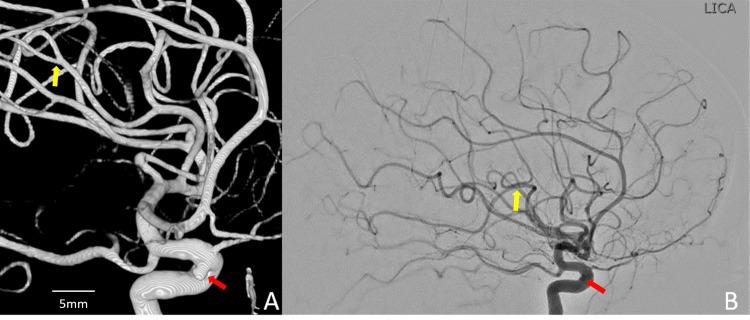

Despite significant diagnostic and technical progress in managing intracranial aneurysms, there are still open questions in understanding their pathophysiology: how fast can they form and grow? We had the chance to observe the "de novo" genesis and rupture of an aneurysm of a left MCA posterior trunk M3 branch within 14 days in one of our patients. We were in the position to compare an initially inconspicuous vessel, assessed during a diagnostic cerebral angiogram with 3D acquisitions, performed as an elective follow-up to monitor the decade stability of a transitional aneurysm in the same vascular territory, and the same vessel only two weeks after, harboring a new small ruptured aneurysm. Several studies along the intracranial aneurysms' pathophysiology have been reported but primarily oriented toward identifying uncommon conditions such as inherent defects in collagen synthesis, genetic or familial factors, or basic anatomic variations or abnormalities in the cerebral vasculature. Suppose this case report does not pretend to provide a clear answer to these questions. However, it is up to date, the shortest time (14 days) reported in the literature for a well-documented "de novo" genesis and rupture of an intracranial aneurysm "in vivo" in humans. The purpose of this case report is not only to underscore the unpredictability of this vascular disease but, even more, to support the idea that further investigation, with more modern methodologies, is of paramount importance in determining the etiopathogenesis and behavior of this stealthy disease.

尽管在颅内动脉瘤的管理方面取得了重大的诊断和技术进展,但在理解其病理生理学方面仍存在一些悬而未决的问题:它们形成和生长的速度有多快?我们有机会在我们的一名患者中观察到左侧大脑中动脉后干M3分支的动脉瘤在14天内“从头”发生和破裂。我们能够将在诊断性脑血管造影中通过三维采集评估的最初不显眼的血管,与在同一血管区域对一个过渡性动脉瘤进行十年稳定性监测的选择性随访中进行的造影进行比较,以及仅在两周后观察到同一个血管,此时它出现了一个新的小破裂动脉瘤。关于颅内动脉瘤病理生理学的几项研究已经报道,但主要侧重于识别罕见情况,如胶原合成的内在缺陷、遗传或家族因素,或脑血管系统的基本解剖变异或异常。假设本病例报告并非旨在为这些问题提供明确答案。然而,它是最新的,是文献中报道的人类颅内动脉瘤在“体内”有充分记录的“从头”发生和破裂的最短时间(14天)。本病例报告的目的不仅是强调这种血管疾病的不可预测性,更重要的是支持这样一种观点,即采用更现代的方法进行进一步研究对于确定这种隐匿性疾病的病因和行为至关重要。